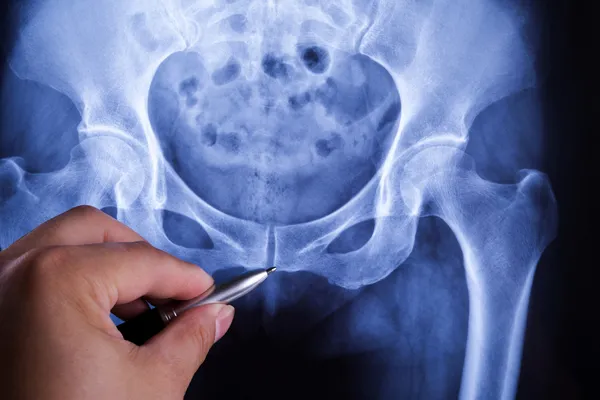

Omurganızın tabanında kronik ağrı yaşıyorsanız, sorunu tanımlamak için bir dizi röntgen MR ve BT taraması gerekebilir. Bu hastalarda görülen yakınmalar;